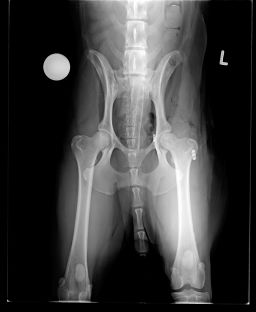

Voici les radios du 23 octobre... la tête du fémur est nécrosée...sur problème infectieux... je ne suis pas contente... la seule alternative qu'il reste maintenant et de tout enlever, de couper la tête du fémur... et Twarak devra vivre ainsi.

Il me dise que pour un chien comme lui, c'est très gérable... je suis triste pour Twarak....